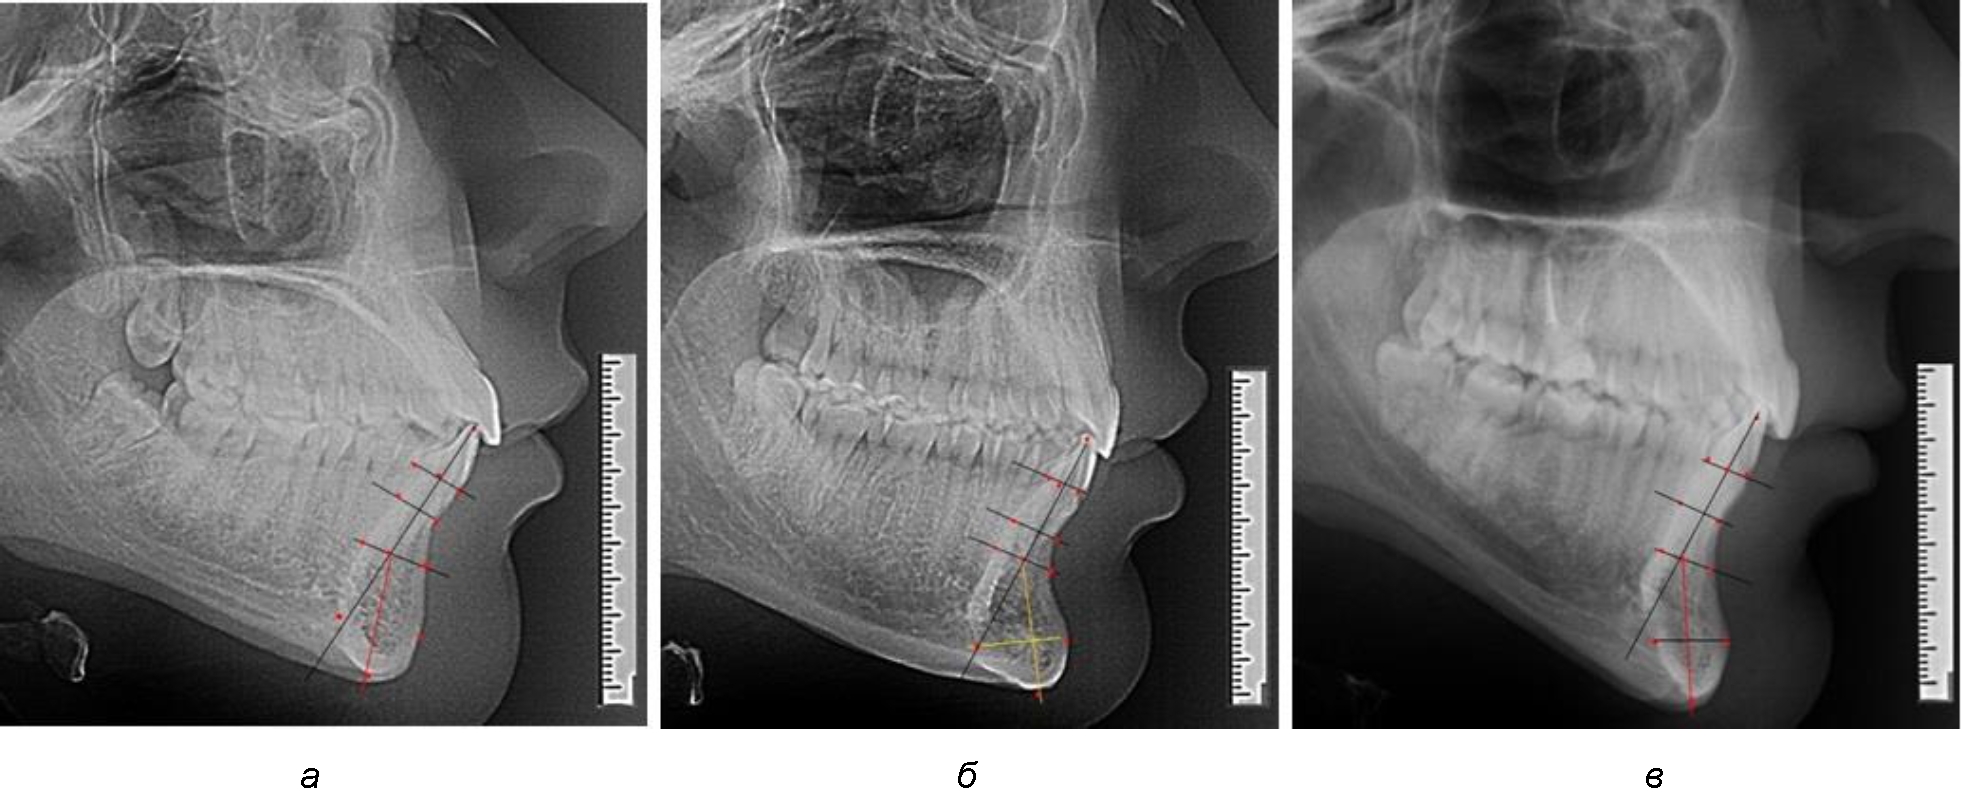

На нижнем контуре подбородочного выступа определяли положение ментальной точки Me. Линия, соединяющая апикальную точку с ментальной, определяла высоту подбородочного выступа тела нижней челюсти. Высота зубочелюстного сегмента IsL–Ме измерялась от резцовой до подбородочной точки. Вертикальная линия Ap–Me делила подбородочный выступ на две части: переднюю и заднюю (рис. 1).

Рис. 1. Ориентиры для исследования нативных препаратов (а) и рентгенограмм (б) резцового нижнечелюстного сегмента

Сагиттальные размеры зубоальвеолярной части сегмента определялись между точками Bsm и Bsm', в апикальной части сегмента – B и B'. В подбородочной части сегмента из передней выступающей точки подбородка Pog проводили линию перпендикулярно к линии Ар–Ме с определением точки Pog'. Расстояние Pog–Pog' определяло ширину подбородочного выступа.

Рис. 3. Варианты среднего (а), широкого (б) и узкого (в) нижнечелюстного резцового сегмента

Варианты резцовых сегментов нижней челюсти различные как по ширине, так и по высоте, а также по расхождению положения апикальных точек по Downs и Schwarz представлены на рис. 4.

Рис. 4. Особенности нижнечелюстного резцового сегмента на ТРГ у людей при среднем (а), широком (б) и узком (в) вариантах